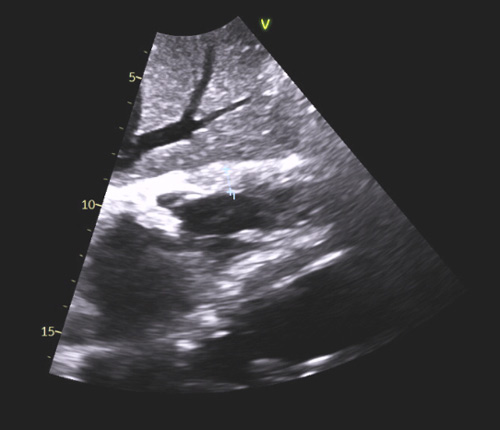

L’atteinte cardiaque secondaire à une amylose se présente généralement sous forme d’hypertrophie biventriculaire avec une hypertrophie ventriculaire gauche le plus souvent concentrique ou diffuse (Figure 1a), qui peut cependant parfois être modérée (12-13 mm). Généralement non obstructive, cette hypertrophie peut prédominer au niveau du septum interventriculaire et même prendre parfois l’aspect d’une cardiomyopathie hypertrophique sarcomérique. Il convient donc de la suspecter devant toute hypertrophie ventriculaire gauche (VG), surtout si celle-ci est concentrique ou diffuse, et si elle s’associe à d’autres éléments comme une hypertrophie de la paroi du ventricule droit (VD) (épaisseur de paroi >5 mm lors de la mesure réalisée en incidence sous-costale) (Figure 1b) avec dysfonction systolique assez fréquente sans être systématique.

Figure 1 : Aspects morphologiques échocardiographiques typiques d’amylose cardiaque

a- HVG concentrique diffuse avec dilatation biatriale